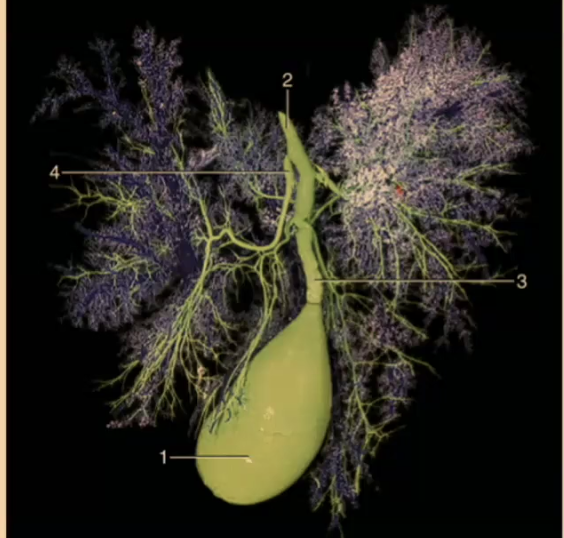

How many lobes are there to the liver?

4

What are the 4 lobes of the liver?

Left, Quadrate, Right, Caudate

#2?

Medial

#1?

Lateral

#3?

Quadrate

#4?

Medial

#5

Lateral

#6 & #7

Caudate

What produces bile?

Liver

#2

Bile duct

#1

Gallbladder

What animal is there no gallbladder?

Horse

Where is the bile stored?

Gallbladder